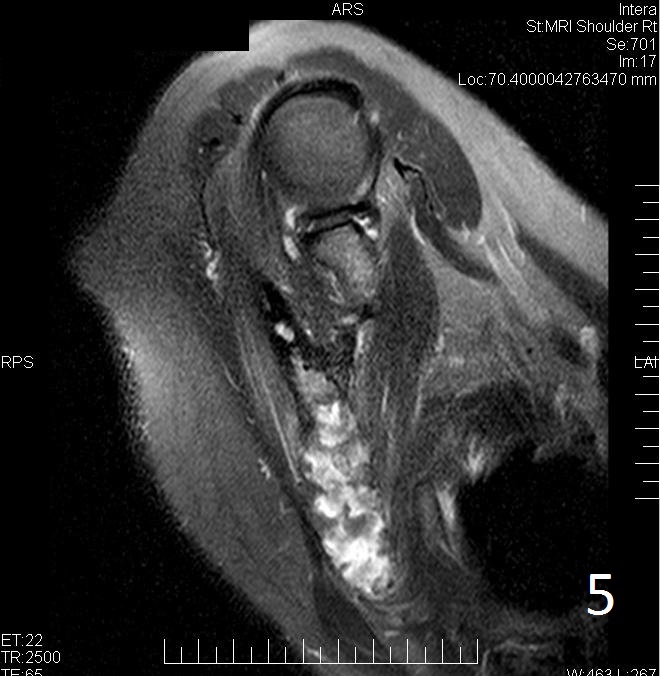

MRI

• MRI can have a very variable appearance and enhancement pattern; May not follow same signal as fibrous tissue which is normally Low signal on T1 and T2

• Variable heterogeneous signal on T2 (Fig. 5)

Fig. 5. Same lesion on Axial T2W FS shows heterogenous signal.